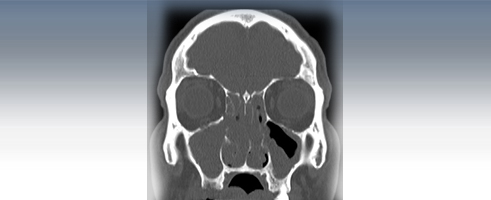

A CT scan is a diagnostic test that takes cross sectional pictures of the patient's internal anatomy. A CT scan creates highly detailed, cross sectional images of body parts and internal organs. CT can show bone and soft tissue structures such as internal organs, muscles, and blood vessels. It can be utilized to detect and diagnose a wide variety of medical conditions and abnormalities of nearly any body organ. A CT scan may require a contrast media such as barium or IV contrast to better highlight abnormalities. These examinations are performed by certified technologists, and every examination is directly supervised and interpreted by board certified radiologists.

A CT scan is made up of a series of x-rays which are processed by a computer to produce cross-sectional pictures of the body. These cross-sectional images allow one to look at the inside of the body.

CT Studies Offered:

- Sinus